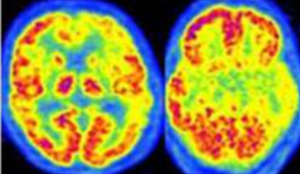

La medicina nucleare, attraverso tecniche come la SPECT cerebrale (che misura il flusso sanguigno regionale, rCBF) e la PET con FDG (che valuta il metabolismo del glucosio, rCGM), riveste un ruolo fondamentale nel distinguere queste diverse forme. Sebbene i meccanismi misurati (flusso e metabolismo) siano diversi, le due metodiche rivelano pattern scintigrafici molto simili per ogni tipo di demenza, agendo come una “finestra” sull’attività funzionale del cervello.

Un esame normale, sia SPECT che PET, mostrerà un’immagine uniforme e simmetrica del consumo energetico cerebrale, senza aree di ipoperfusione o ipometabolismo significative.

Il Morbo di Alzheimer, la forma di demenza degenerativa progressiva più comune, presenta un’impronta caratteristica che la medicina nucleare è in grado di identificare con grande precisione. Il quadro tipico mostra una riduzione generalizzata del flusso sanguigno e del metabolismo, ma con un’accentuazione marcata del deficit nelle regioni posteriori temporo-parietali bilaterali e nella corteccia cingolata posteriore.

Al contrario, aree come il talamo, i nuclei della base (striato) e la corteccia sensomotoria rimangono relativamente risparmiate nelle fasi iniziali della malattia. I lobi frontali tendono a essere coinvolti in una fase più avanzata del decorso patologico. Questo pattern distintivo permette di differenziare l’Alzheimer da altre demenze con un’accuratezza molto elevata, supportando una diagnosi precoce e un approccio terapeutico più mirato.